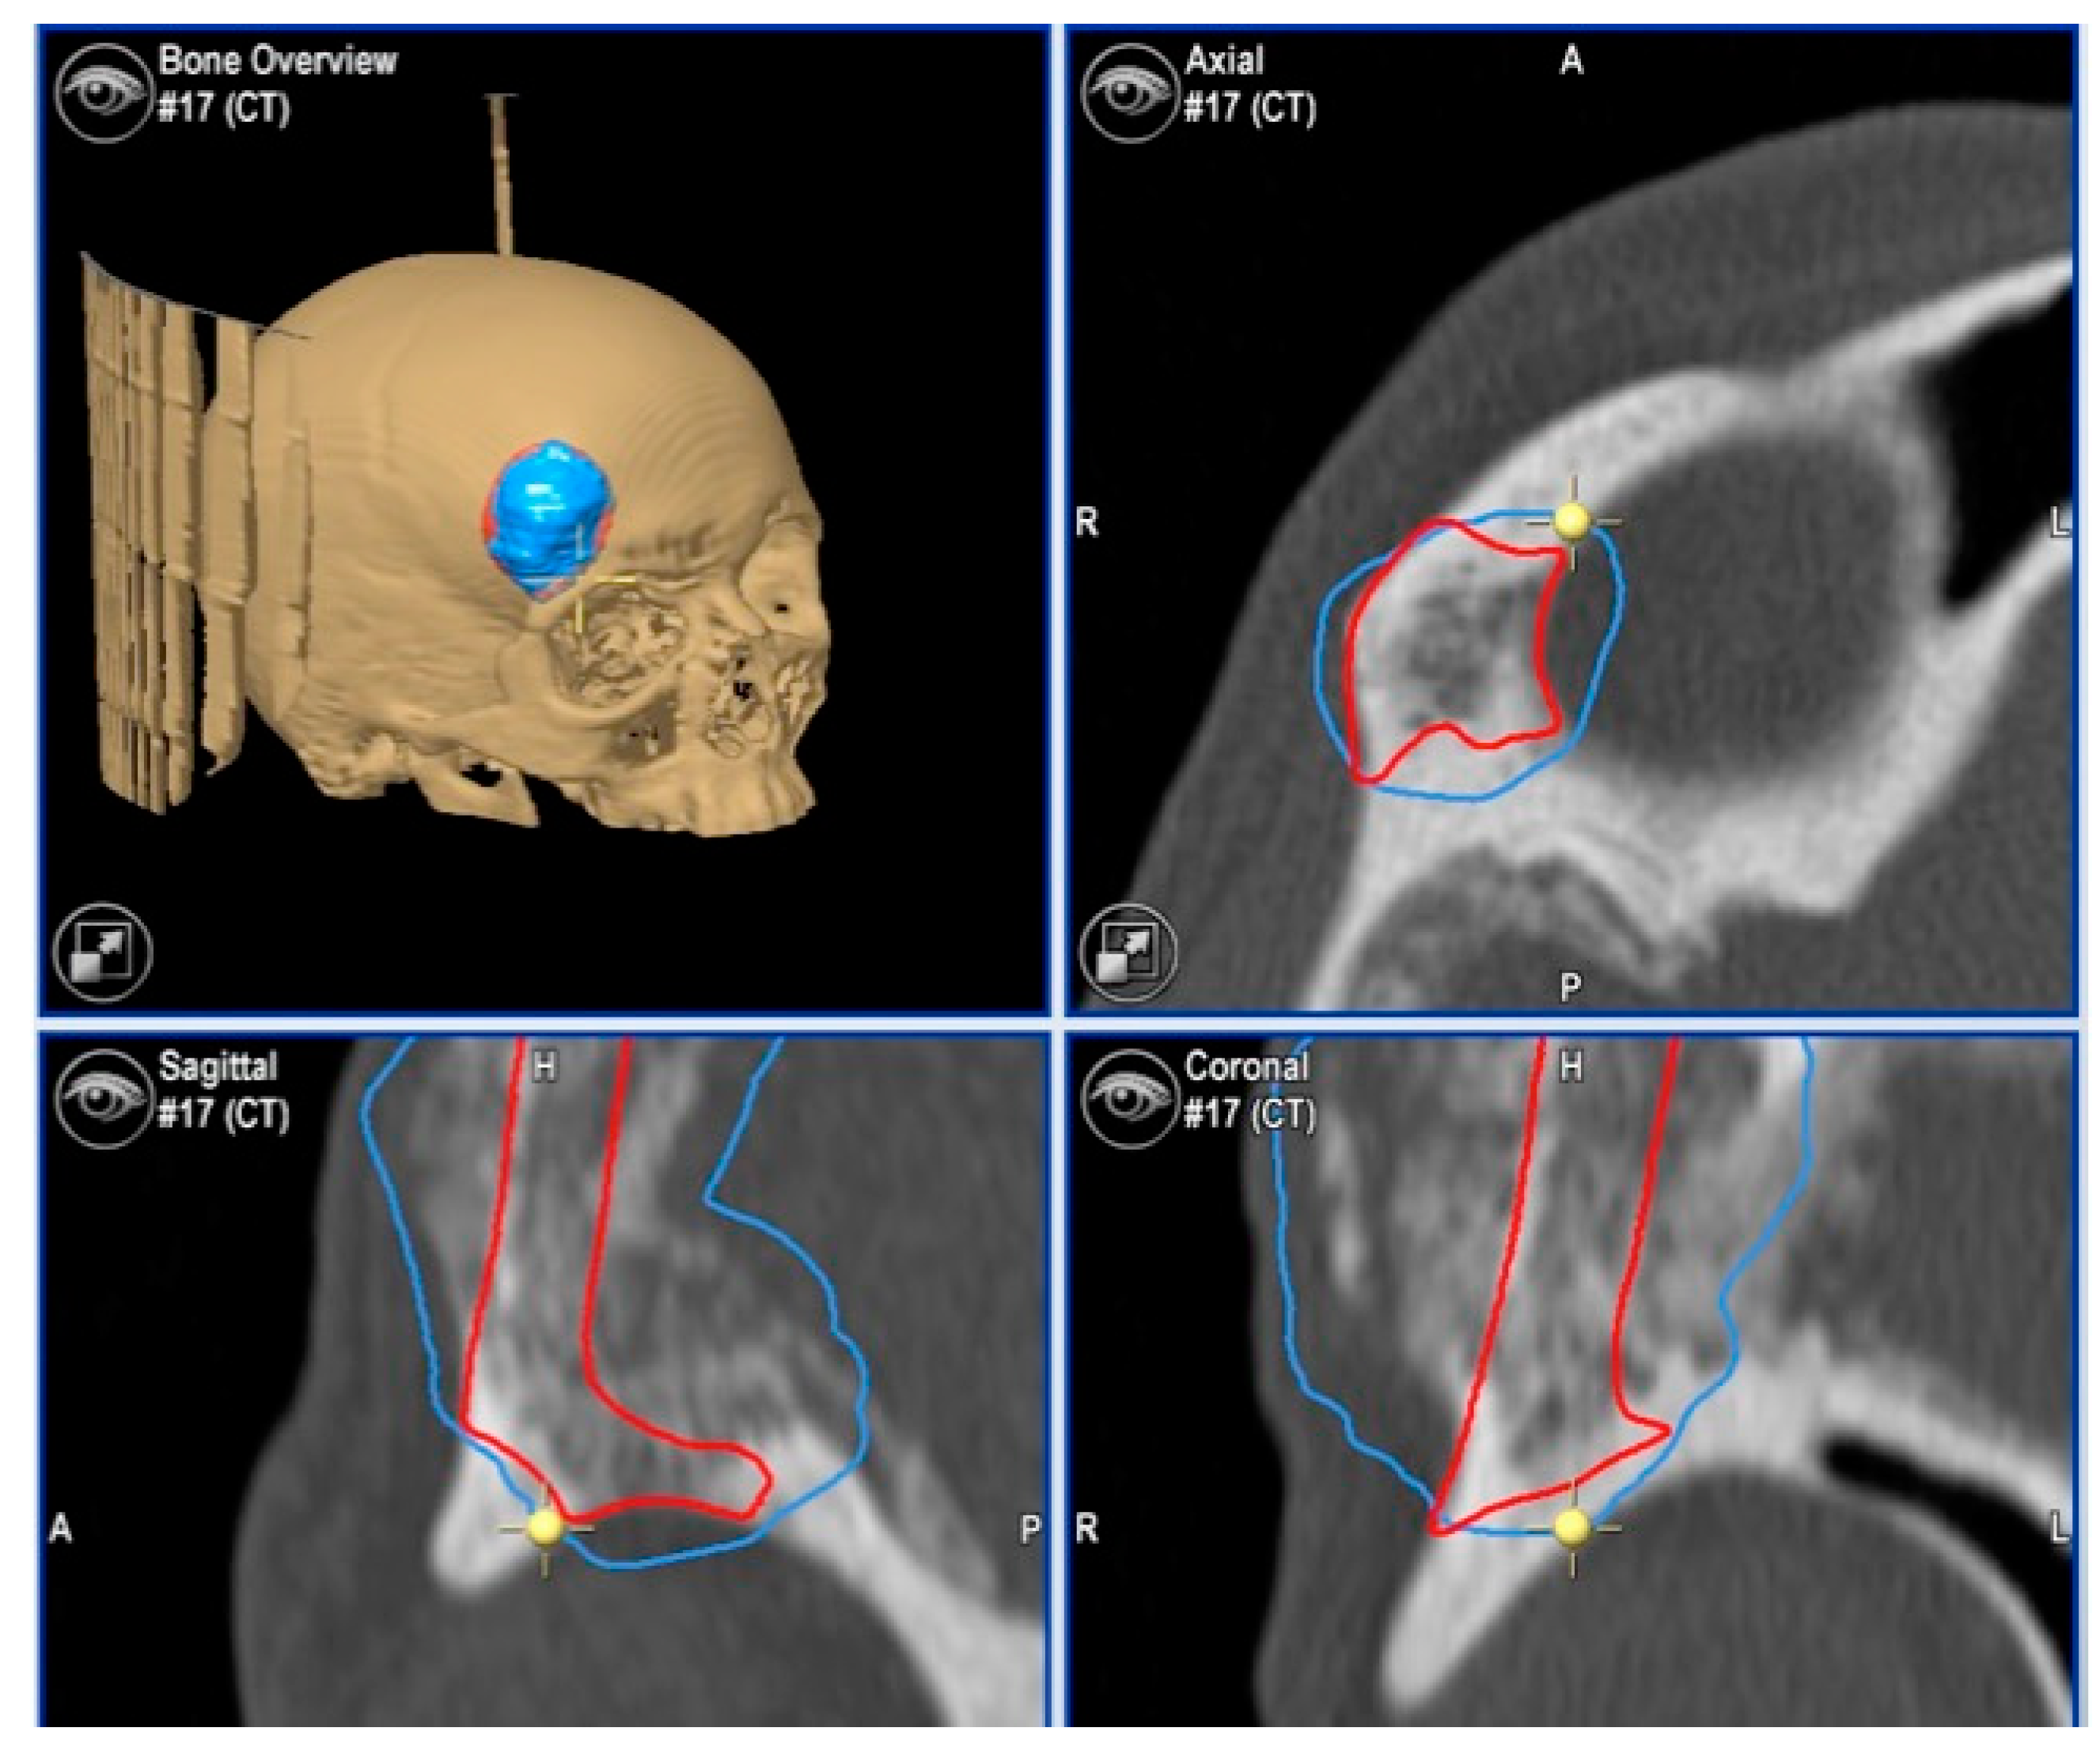

2.3.1. Virtual Surgical Plan

2.3.2. CAD-CAM Design of the PEEK Prosthesis

| 1 | 53/F | L/25 mm | Y | 4 mo | Dystopia | N | CT, MRI | Supraorbital rim, orbital roof | Intraosseous venous malformation | - | Resection + reconstruction | Y | Y | 1st, 2nd, 3rd | Coronal | Y | Piezoelectric device | N | PEEK prosthesis | 7 y/N |

| 2 | 54/F | R/33 mm | Y | 9 y | N | Y | CT, MRI | Frontal bone, orbital roof | Intraosseous venous malformation | - | Resection + reconstruction | Y | Y | 1st, 2nd, 3rd | Coronal | Y | Piezoelectric device | N | PEEK prosthesis | 6 y/N |

| 3 | 36/F | L/19 mm | Y | 6 mo | N | N | CT, MRI | Zygoma | Arteriovenous malformation | - | Resection + reconstruction | Y | Y | 1st, 2nd, 3rd | Transconjunctival + blepharoplasty + maxillary vestibular | Y | Piezoelectric device | N | PEEK prosthesis | 5 y/N |

| 4 | 47/M | L/30 mm | N | 2 y | N | N | CT | Zygoma | Intraosseous venous malformation | - | Resection + reconstruction | Y | Y | 1st, 2nd, 3rd | Transconjunctival + lateral canthotomy + maxillary vestibular | Y | Piezoelectric device | N | PEEK prosthesis | 6 y/N |